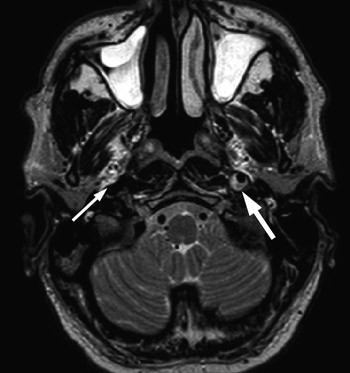

De fleste isolerte Horners syndrom er postganglionære og kan volde diagnostisk hodebry. Carotisdisseksjon er en av de viktigste årsakene som bør utelukkes. Utredning med MR-angiografi er å foretrekke fremfor CT (og ultralyd), da disse undersøkelsene er for lite sensitive, spesielt ved disseksjoner i nærheten av skallebasis (21). Også konvensjonell angiografi kan være utilstrekkelig dersom lumen av karet ikke innsnevres (22). Horners syndrom ledsaget av parese i 3., 4., 5. eller 6. hjernenerve gir mistanke om lesjon i sinus cavernosus, i det paratrigeminale området eller i orbitale apex. Ved mistanke bør man utføre grundige, fokuserte MR-undersøkelser av disse områdene.